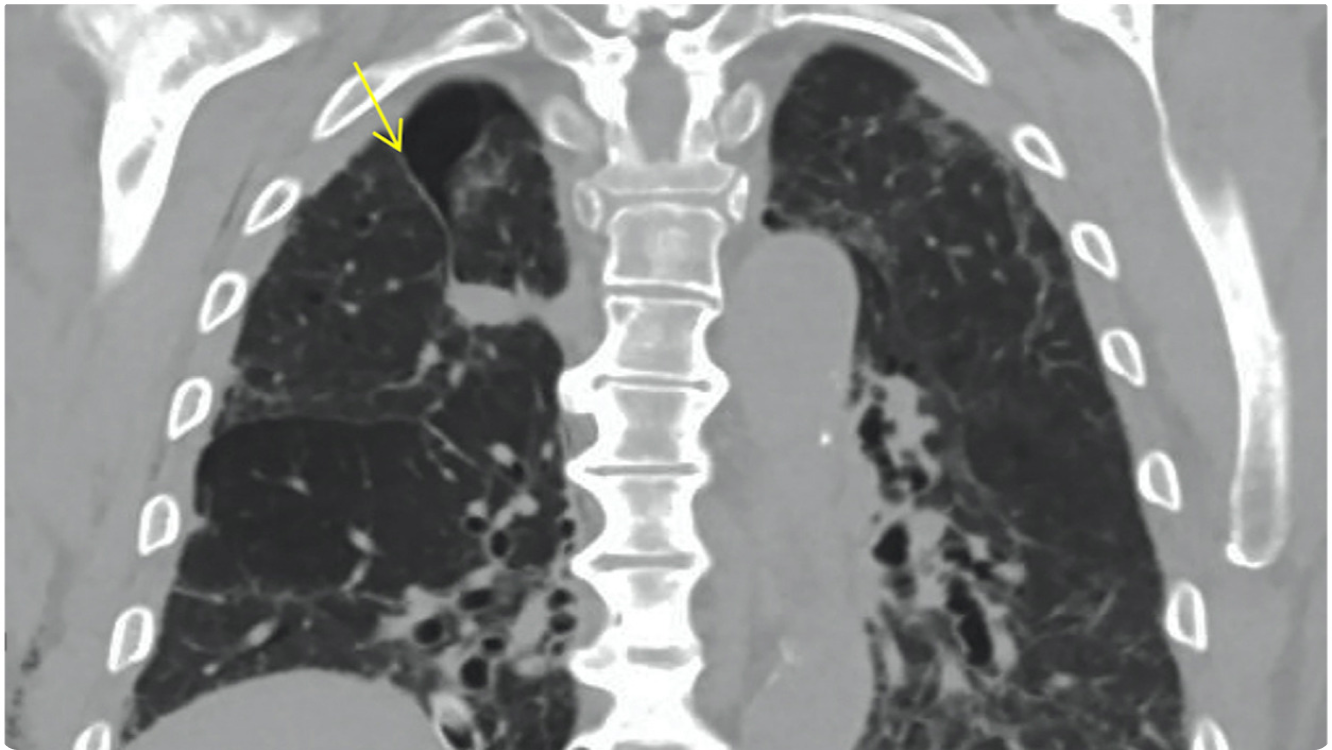

An Azygos lobe fissure is seen on right side. It extends from the lateral aspect of the vertebral body posteriorly, to the right brachiocephalicvein and SVC anteriorly.

• An azygos lobe is a rare normal anatomic variant of the right upper lobe, first described by Heinrich Wrisberg in 1778 due to invagination of the azygos vein and pleura during fetal development.

• An azygos lobe is created when a laterally displaced azygos vein creates a deep pleural fissure into the apical segment of the right upper lobe during embryological development.